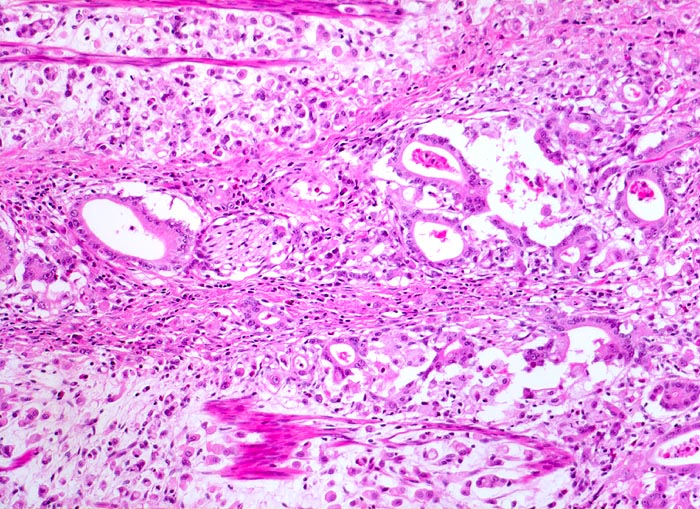

PathoPic – image database / PathoPic ID 3385 - Adenokarzinom des Magens mit Siegelringzellen

Adenokarzinom des Magens mit Siegelringzellen

Ein Grossteil des Tumorinfiltrats besteht aus einzeln liegenden Siegelringzellen. Ein Teil der Tumorzellen bildet Drüsenschläuche (Mischtyp nach Lauren). Tumorinfiltration einer Nervenscheide. Zwischen den Tumorzellen Reste der glatten Muskulatur der Magenwand.

Der histologische Subtyp eines Siegelringzellkarzinoms darf dann diagnostiziert werden, wenn die Siegelringzellen mindestens 50% der Tumormasse ausmachen.